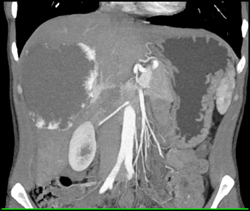

Hepatoblastoma